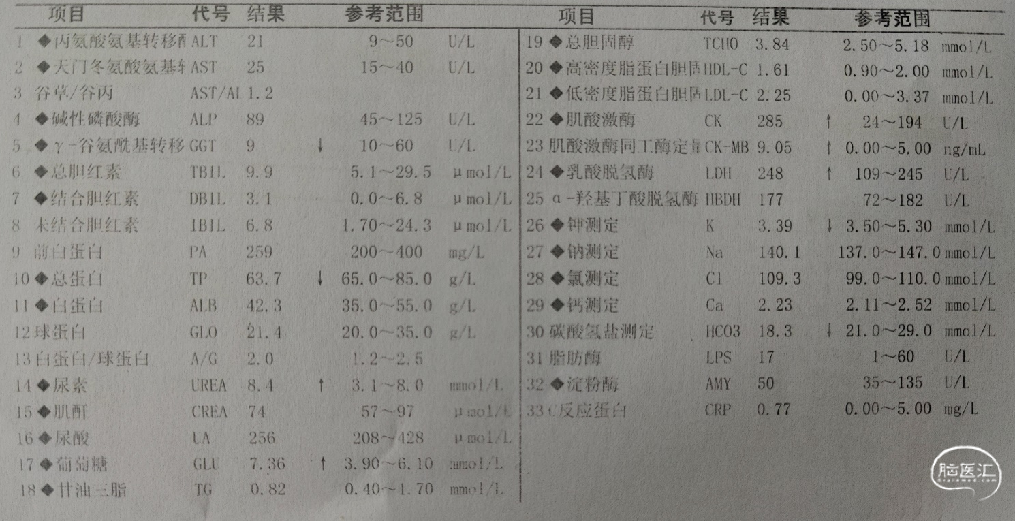

入院检查

![]()

入院化验

积极纠正凝血功能:氨甲环酸1g